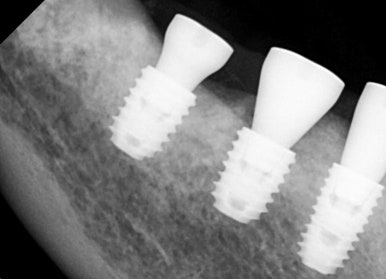

뼈이식을 동반하여 새로운 임플란트 식립이 깔끔하게 잘 이루어 졌고,

수술 후 2개월 정도 회복 기간을 가진 뒤에, 보철 과정을 진행하였습니다.

아래는 치료가 완료된 모습입니다.